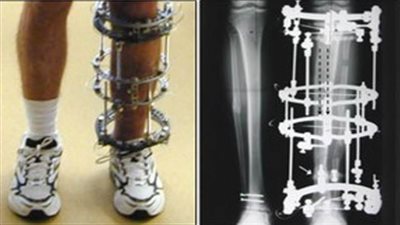

الْيوم.. مستجدات "اصلاح تشوهات واطالة العظام" في ملتقى "الأطباء العرب" عبر الإنترنت

غداً.. انطلاق مؤتمر إصلاح تشوهات العظام بالقاهرة